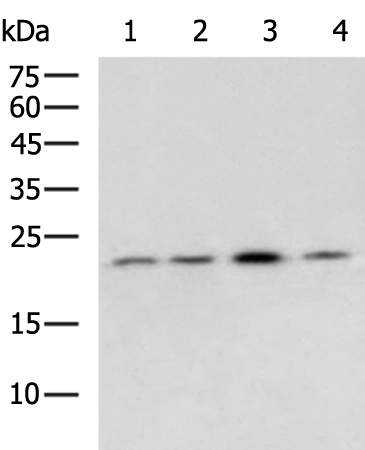

分类: 科研抗体货号: P06988别名: BCL2L4应用: WB,IHC反应种属: Human, Mouse, Rat